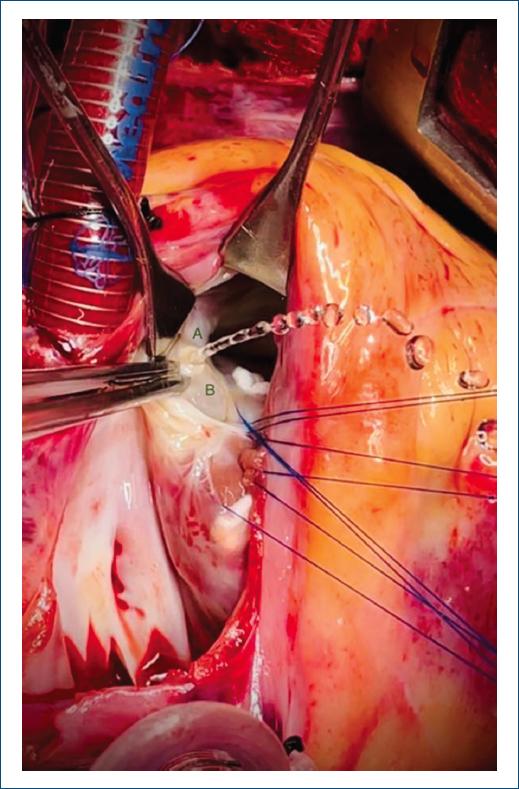

El síndrome de Laubry-Pezzi es una malformación cardiaca no sindromática y poco frecuente, caracterizada por una comunicación interventricular (CIV) e insuficiencia aórtica, las cuales producen prolapso de la valva coronariana derecha y menos frecuente de la valva no coronariana1. Presentamos el caso de un paciente de 14 años con presencia de soplo cardiaco en etapa preescolar diagnosticándose una comunicación interventricular subaórtica con prolapso valvular aórtico e insuficiencia aórtica moderada (Fig. 1). En las valoraciones subsecuentes presenta disminución en la clase funcional y ecocardiográficamente incremento de la insuficiencia aórtica, por lo que se decide cierre del defecto. Durante el procedimiento quirúrgico se realiza prueba hidráulica identificando prolapso y perforación de valva no coronariana de aproximadamente 5 x 8 mm de diámetro (Fig. 2), lo cual es sumamente infrecuente. La asociación de CIV infundibular con prolapso e insuficiencia aórtica es rara, con una incidencia aproximada del 5 al 10%, siendo el prolapso progresivo y con presencia de defectos pequeños; se ha observado que tienden a evolucionar con mayor rapidez la insuficiencia aórtica2. Al ser una patología poco frecuente, la decisión de intervención quirúrgica es un tema controvertido, sin embargo, algunos autores refieren que debe considerarse al igual que cualquier defecto interventricular, es decir, se debe realizar el cierre quirúrgico cuando se observe insuficiencia aórtica independientemente de la repercusión hemodinámica de la cardiopatía, ya que el desarrollo de esta puede complicar el pronóstico y la supervivencia del paciente2.